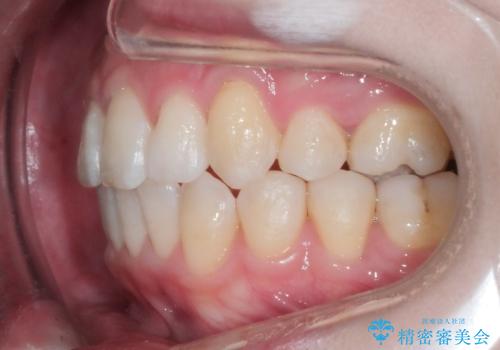

- 上顎の八重歯が気になるとのことで来院されました。

左側のかみ合わせは、歯1本分かみ合わせが前にずれていました。上顎左右の奥歯を2本抜歯しています。

八重歯でがたつきは重度でしたが、きれいな歯並びにすることができました。

がたつきだけでなく、奥歯の噛み合わせのずれの調整もしっかり行いました。